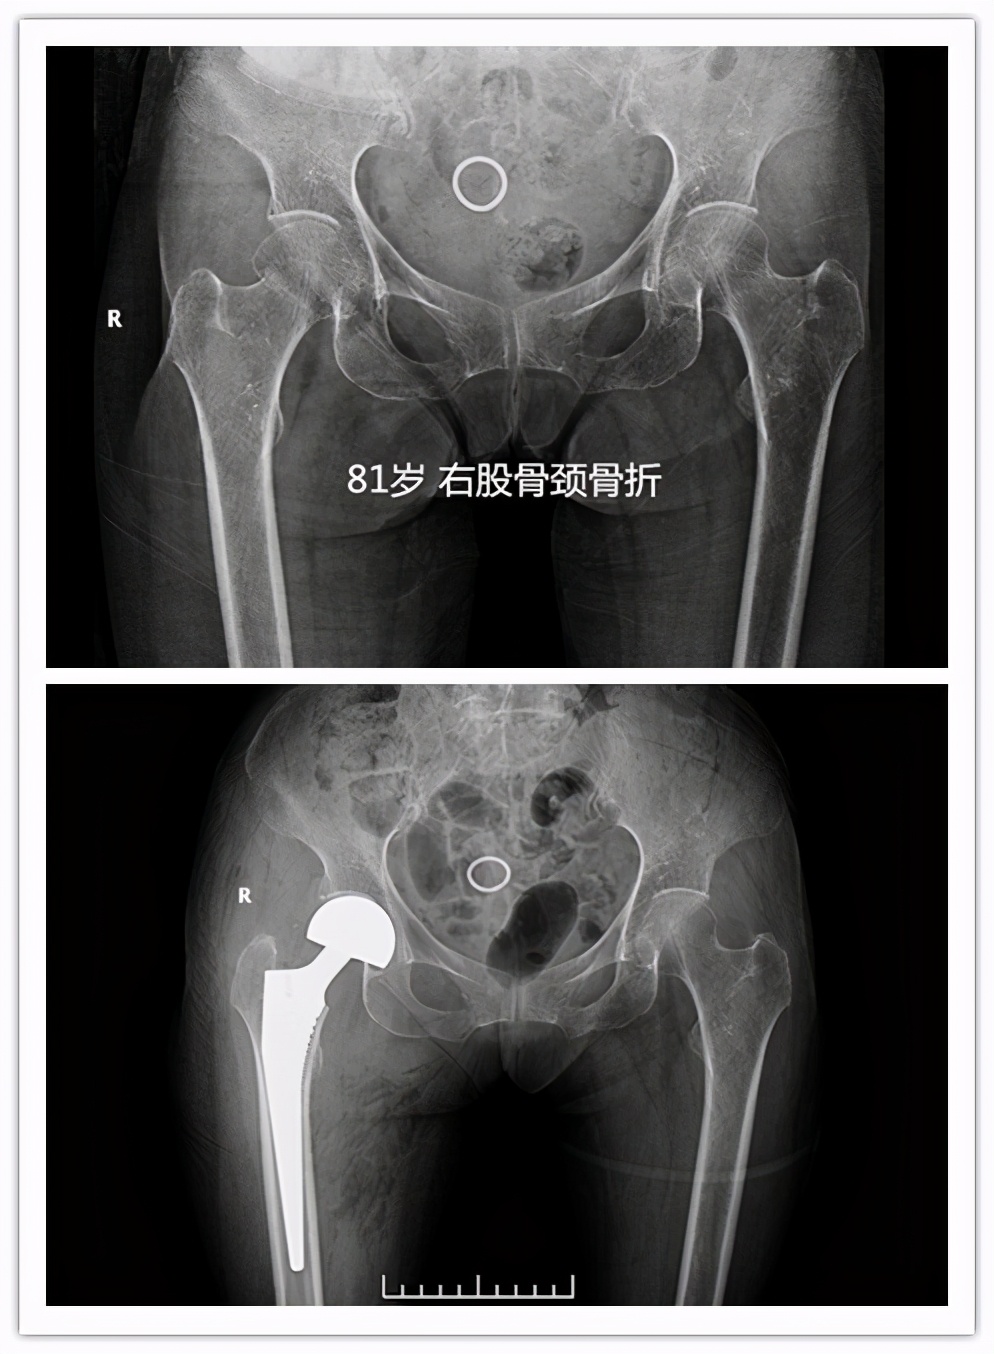

- 对于老年高龄的股骨颈骨折患者,一般可能人工股骨头置换手术,手术时间短,术后1-2日病人可早期下床活动,降低卧床并发症,提高患者生活治疗。对于粗隆间骨折,可行PFNA或者人工股骨头置换手术。

很多家属最大疑问:我们家的老人都七八十岁了,还能做手术吗?其实跌倒后出现髋部骨折多大出现于老年高龄患者,近两年我们科室做的因股骨颈骨折行人工股骨头置换手术最大年龄为 99岁 ,老人家术后2日扶助行器下床活动。 所以老人是否能耐受手术,不能只看年龄 ,需要请医师进一步进行术前评估。通过手术治疗,病人可尽早离开床,尽快恢复日常生活,提高患者生活质量,降低死亡率。